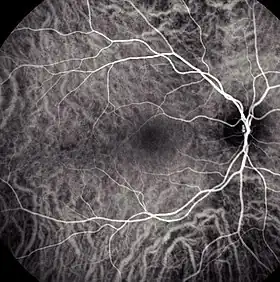

![]() Choroidal blood flow revealed with indocyanine green angiography | |

Indocyanine green angiography (ICGA) is a diagnostic procedure used to examine choroidal blood flow and associated pathology. Indocyanine green (ICG) is a water soluble cyanine dye which shows fluorescence in near-infrared (790–805 nm) range, with peak spectral absorption of 800-810 nm in blood.[1][2] The near infrared light used in ICGA penetrates ocular pigments such as melanin and xanthophyll, as well as exudates and thin layers of sub-retinal vessels.[3] Age-related macular degeneration is the third main cause of blindness worldwide, and it is the leading cause of blindness in industrialized countries.[4] Indocyanine green angiography is widely used to study choroidal neovascularization in patients with exudative age-related macular degeneration.[5] In nonexudative AMD, ICGA is used in classification of drusen and associated subretinal deposits.[5]